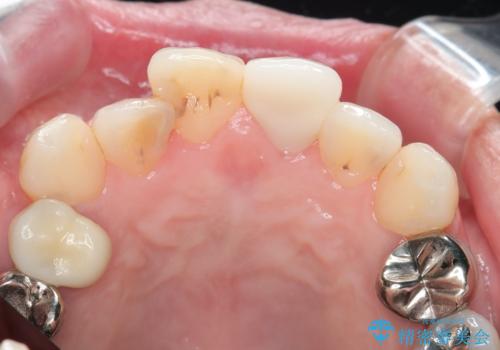

周囲の歯と調和した審美的な仕上がりに満足いただくことができました。

もともと根管治療の為されて歯が折れてしまっているので、根管治療を行い審美的なセラミック治療を行う治療計画としました。

- 15.4万円(ジルコニアクラウン・仮歯・ファイバーコア)費用は治療当時の料金となります